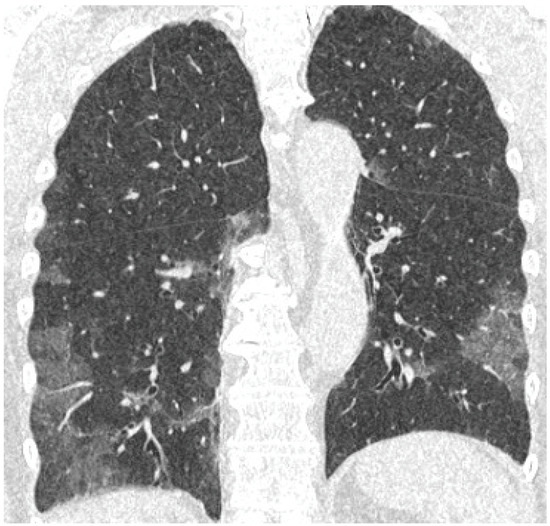

- GGO was defined as hazy increased attenuation of lung with preserved bronchial and vascular margins;

- Consolidation was considered an increase in pulmonary parenchymal attenuation that obscures the airways and vessels;

- Crazy paving was the area of GGO with coexisting thickening of interlobular septae;

- Septal thickening comprised abnormal widening of an interlobular septum or septae;

- Subpleural lines comprised a thin curvilinear opacity of a few millimeters or less thickness usually less than 1 cm from pleural surface and paralleling the pleura.